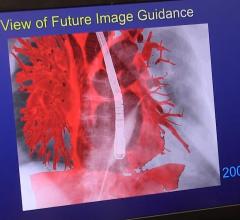

Robert Quaife, M.D., director of advanced cardiac imaging, University of Colorado Hospital, explains why advanced ...